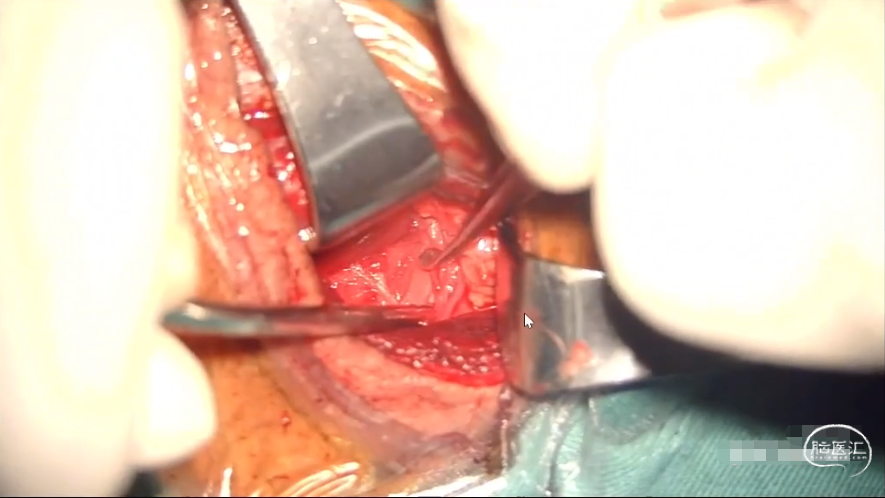

前路手术神经根减压

手术视频截图